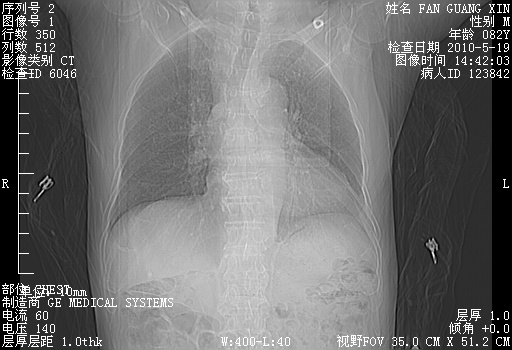

可改为口服强的松40-50mg/d治疗,若病情仍稳定,胸部阴影不再吸收可逐渐减量